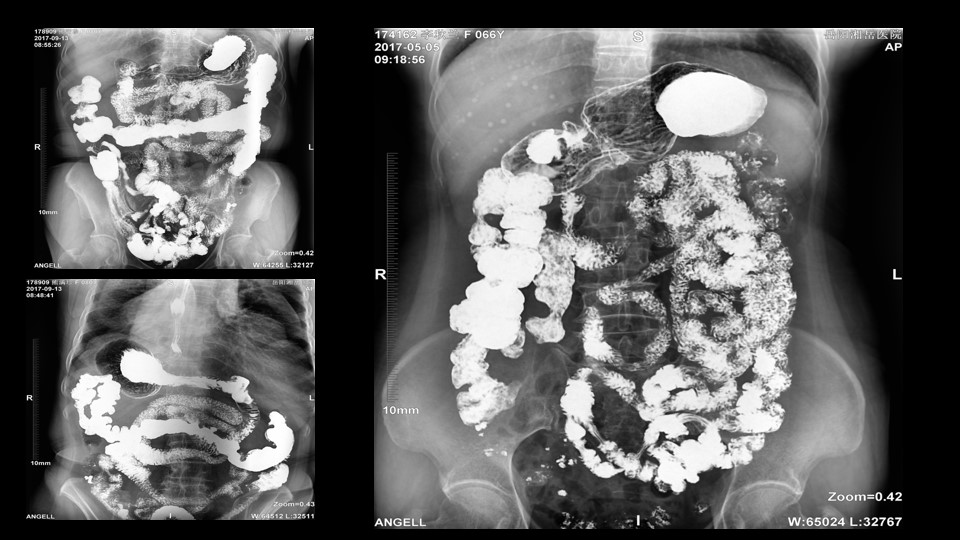

会议开始,岳阳市医学会放射分会副主委、湘岳医院放射科蔡雨主任,结合自身在放射影像的20多年经验,为参会嘉宾分享了动态DR在消化道造影中的应用价值。作为动态DR用户,蔡雨主任结合动态DR的实际拍片与操控经验,分享了动态DR技术在相关群体疾病检查上的独到优势和人文关怀。蔡雨主任说到:“随着内镜技术的发展以及CT、MR的发展,消化道造影在减少,但是这并不意味着消化道造影的价值在下降。以老年人为例,很多老年群体都患有严重的心肺疾病、或者消化道畸形,很多老年人本身就有糖尿病、高血压等等综合疾病,传统内镜的检查对于这类群体来说是一件难以忍受的痛苦,而动态DR的多项创新技术让这类群体的消化系统疾病筛查变得更为人性和精准。任何一个好的消化道造影,一定是患者、诊断医生、临床医生三方满意的结果。388vip太阳集团科技动态DR技术利用900万像素高清拍片、大幅面透视、高清点片、视频保存与回放等核心功能,完全满足临床对消化道气钡双重造影检查的需要。图像质量全面超越以往模拟胃肠机、影增数字胃肠机”。蔡雨主任全面演示了动态DR在食道造影、上消化道造影、小肠双对比造影、结肠气钡双对比造影中的应用,通过动态DR可以清晰获得临床诊断和评估的图像依据。

▲蔡雨主任使用动态造影图像示例